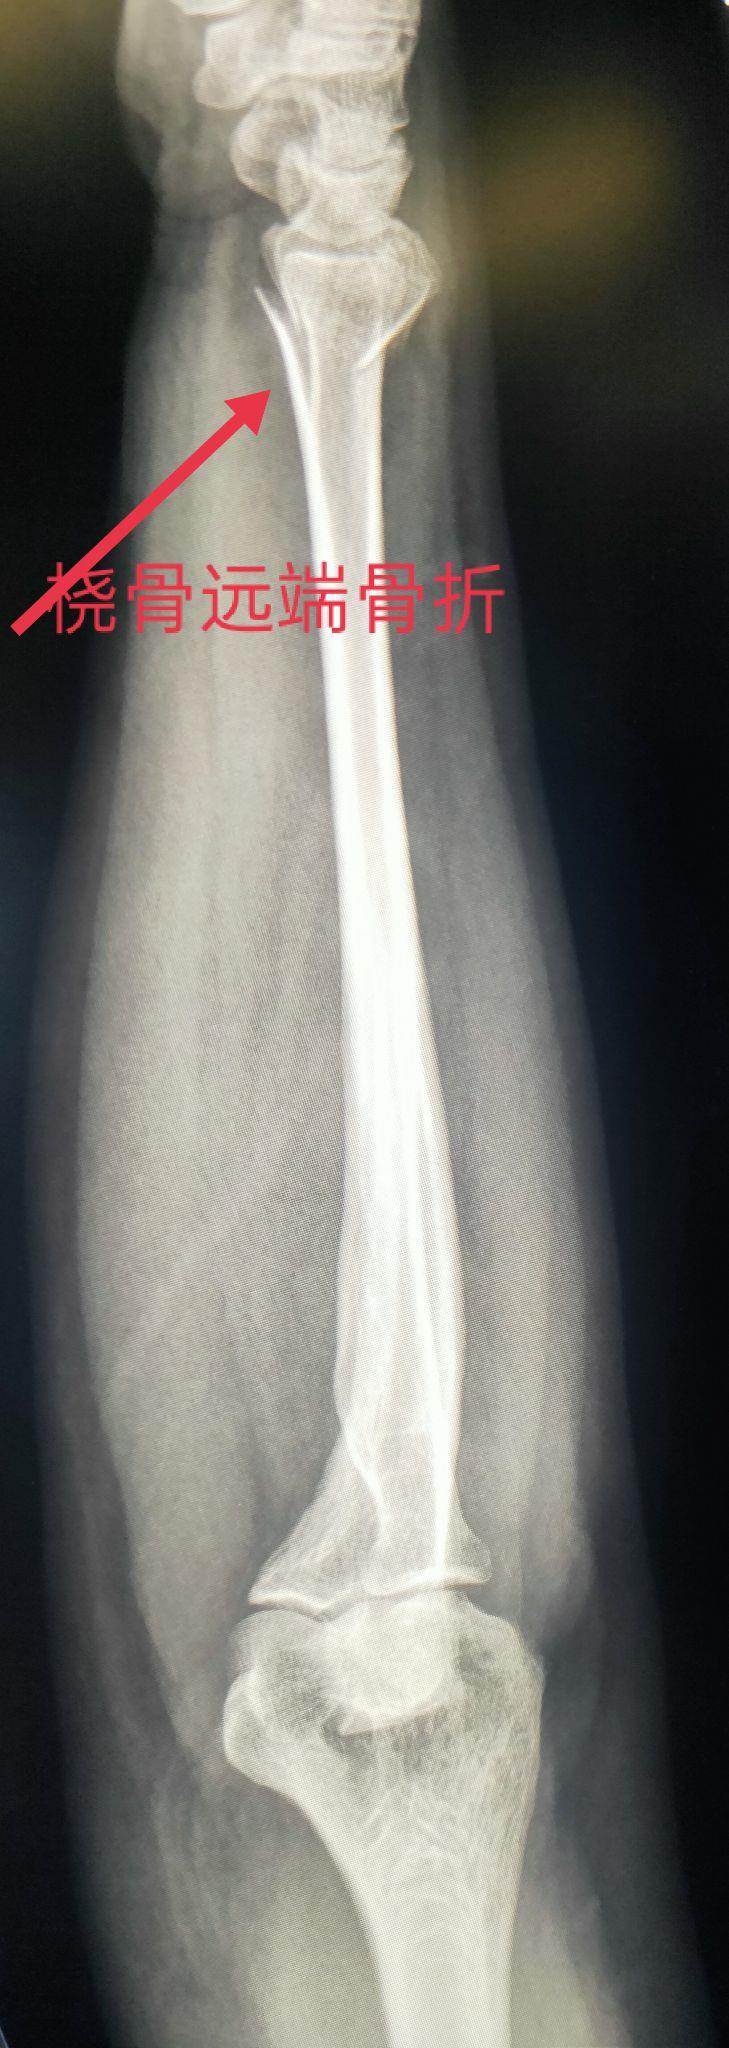

四、尺、桡骨骨折X线片

尺骨桡骨骨折以桡骨远端骨折多见。其次是尺骨桡骨双骨折,多发生于青少年。